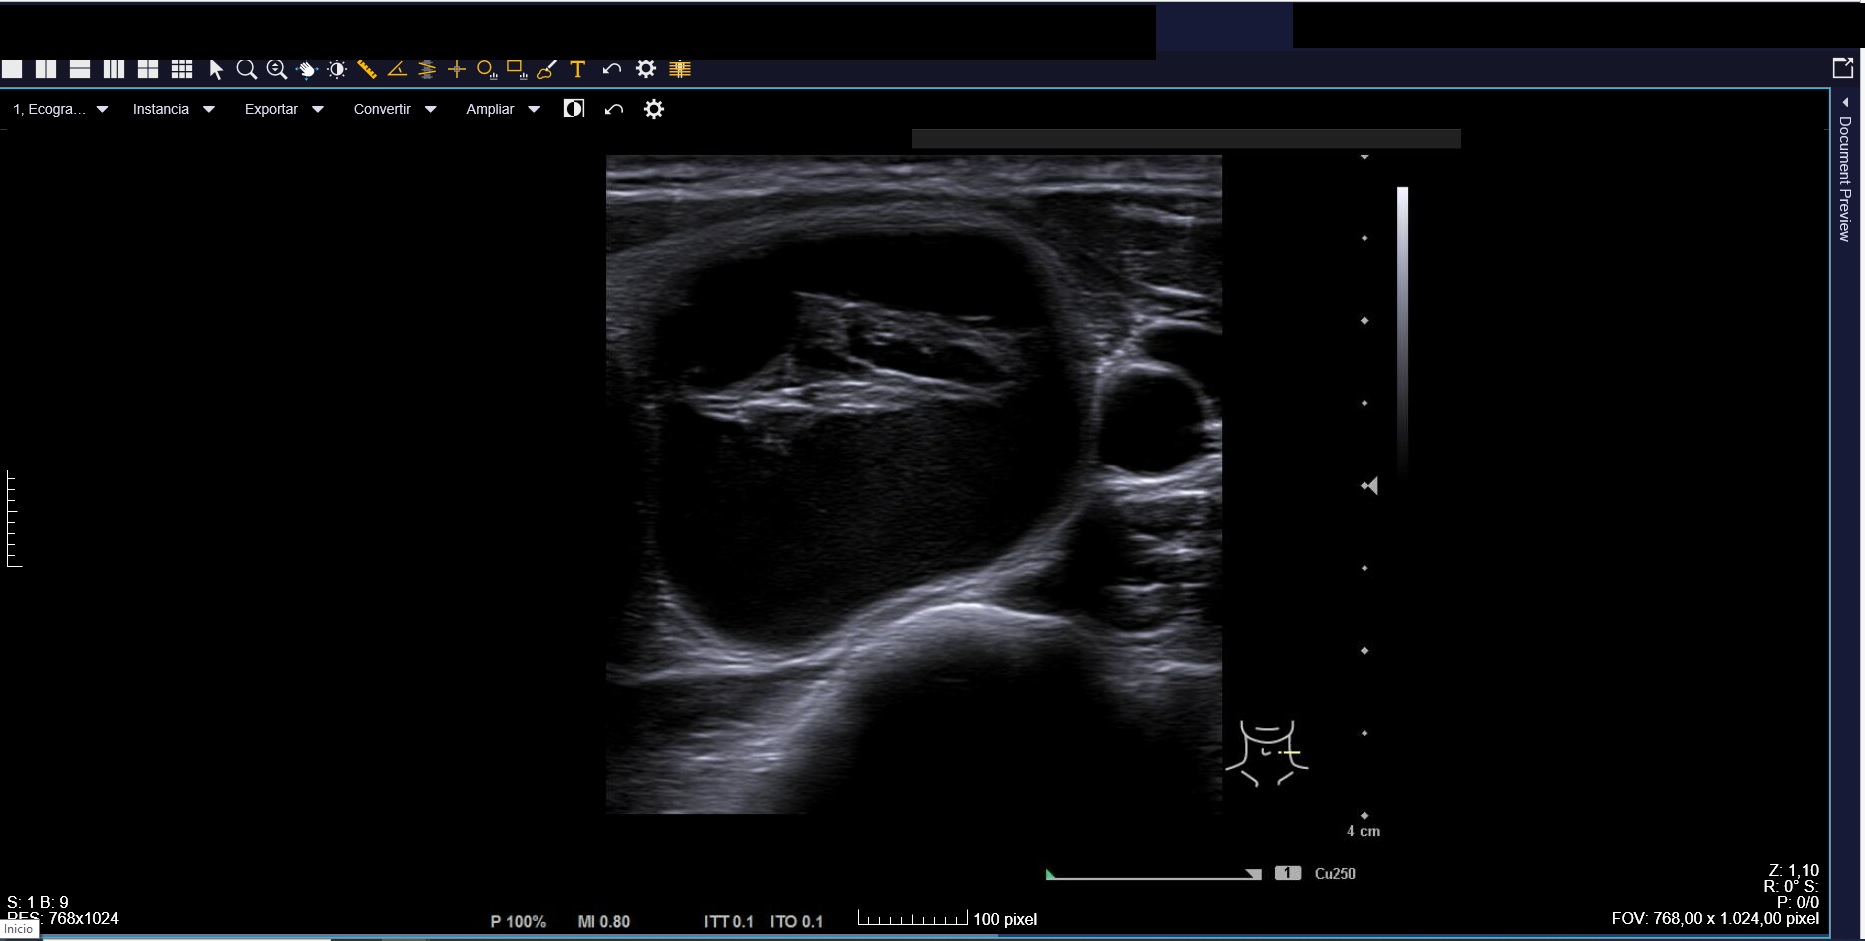

Citamos para seguimiento clínico-ecográfico dos meses después. El bulto había tenido una evolución fluctuante en tamaño pero habían reaparecido las molestias. Nueva ecografía (Imagen 4) confirmó nódulo de características similares a las iniciales, de tamaño ligeramente inferior (2,1 x 2,3 cm). Se observaban focos ecogénicos puntiformes y ecogenicidad indeterminada (TIRADS=4).

Realizamos interconsulta a Endocrinología para valorar PAAF con objetivo diagnóstico-terapéutico.